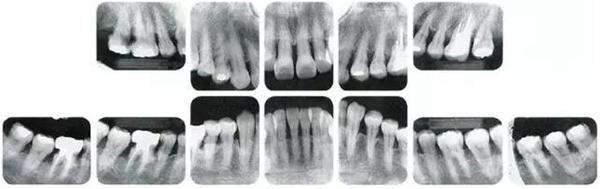

●參考病例① 35歲女性

35歲女性。妊娠4個(gè)月。過(guò)去雖然接受過(guò)刷牙指導(dǎo),但菌斑控制狀態(tài)依然不理想?;颊哂邪l(fā)現(xiàn)自己刷牙時(shí)牙齦出血。

①的患者是35歲女性。4~10mm的牙周袋和大量的牙石。特別是在左上、右下、左下的磨牙處能看到大量牙槽骨吸收。這名患者是慢性牙周炎,僅在磨牙處有局部由風(fēng)險(xiǎn)因子導(dǎo)致(解剖學(xué)形態(tài))導(dǎo)致的重度病癥發(fā)展。